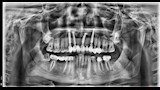

وأشار إسلام إلى أن معاناته بدأت بعد العملية مباشرة، إذ لم تلتئم اللثة رغم مرور ستة أشهر، وبدأ يشعر بإعياء ومشكلات دفعته للتوجه إلى طبيب آخر، والذي طلب منه إجراء أشعة مقطعية وأشعة بانوراما. وقال إنه فوجئ بتشخيص الطبيب بوجود تآكل شديد بعظام الفك العلوي في مواضع الزرع، ووجود خُراجين صديديين، بالإضافة إلى استقرار أحد مسامير الزرعات داخل الجيب الأنفي، وعدم ثبات الزرعات في مكانها.

وقال إسلام في ختام حديثه: «أنا كنت رايح أتعالج.. مش أعمل لنفسي مصيبة صحية»، مؤكدًا أن حالته تستلزم التخلص من الخُراج الصديدي وتنظيف اللثة وإزالة جميع الزرعات وإعادة تركيب أخرى جديدة، بتكلفة قد تصل حسب تقدير الأطباء إلى 150 ألف جنيه وهذا فوق طاقته المادية فضلا عن تكلفة علاج إضافية كما أن إسلام في حاجة لتدعيم عظام الفك بإجراء عملية أخرى بنقل عظام من الفخذ أو الصدر لإصلاح التدهور نتيجة العملية.